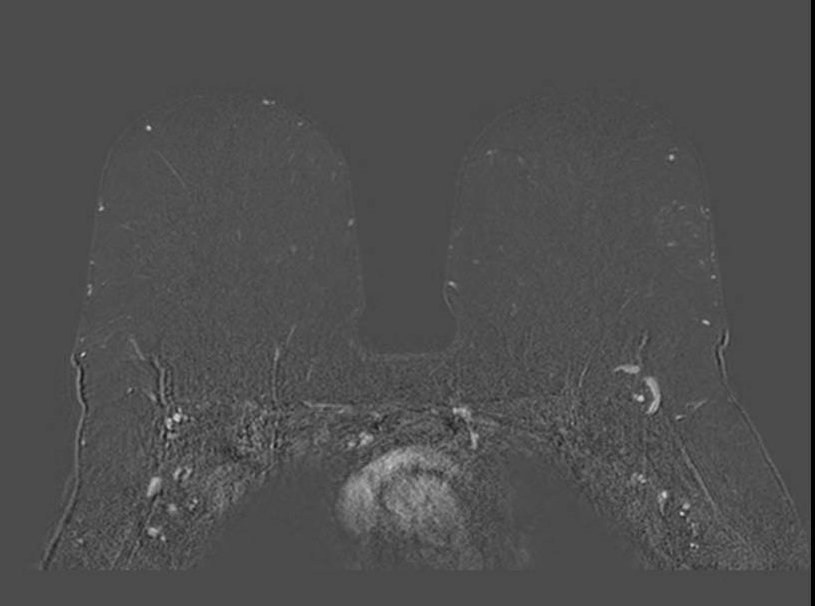

Gibbs ring artifact most noticable at implant interface (axial, IR sequence)

Gibbs ringing is a Fourier truncation artifact from finite k-space sampling. Inverse FFT of truncated data fails to represent the highest spatial frequencies at abrupt transitions, generating thin parallel bright/dark bands near high-contrast boundaries.

In breast MRI, it is easiest to see at skin-air, skin-parenchyma, and implant margins, especially in the phase-encode direction and on high-contrast sequences (e.g., T2). Reduce it by increasing phase-encode steps (more k-space lines) at scan-time cost; zero-fill interpolation can smooth the appearance but does not recover true spatial resolution. Recognition of the characteristic parallel-band pattern of Gibbs ringing helps differentiate it from true lesions.